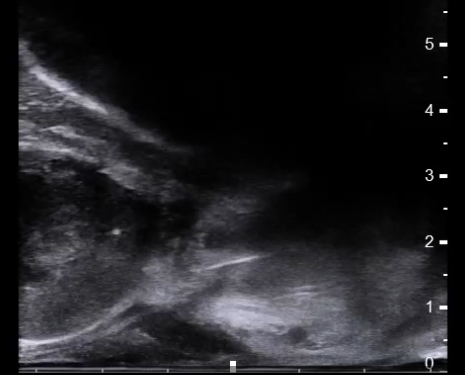

术中超声引导下局麻